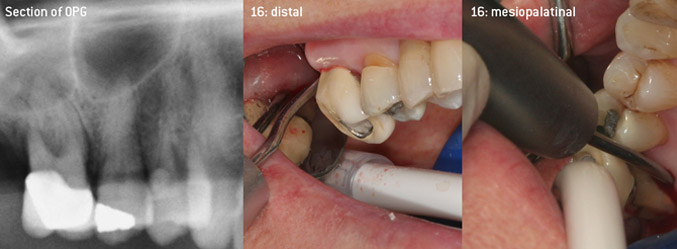

As initiators of the development of the new diamond-coated 3AP air scaler tip, the two dentists recognized the need for improvement of the handling restrictions of the commercially available diamond-coated tips, especially during furcation treatment and when working in tight intraosseous pockets. This should be possible for both non-surgical (Figure 2) and surgical (Figure 3) procedures.

Open debridement of the furcations on teeth 16 and 17

Fig. 3: Open debridement of the furcations on teeth 16 and 17 in case of advanced attachment loss